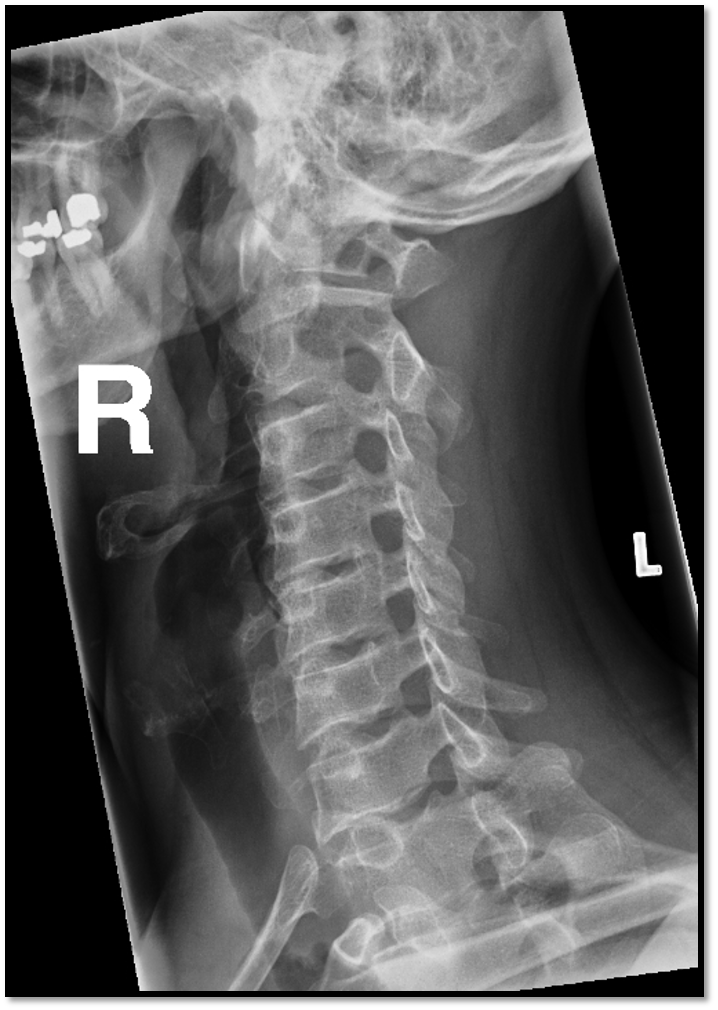

A

• rotation issue: posterior borders arent aligned

• tilt issues: double lines at zygo joints

• need to do swimmers: cant see C7 and T1

• rotation and tilt issue

• swimmers not needed (fusion of C6/C7)